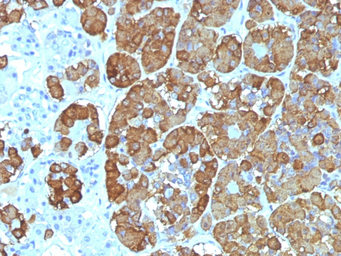

IHC-P analysis of human pituitary tissue using GTX34393 ACTH antibody [CLIP/1449].